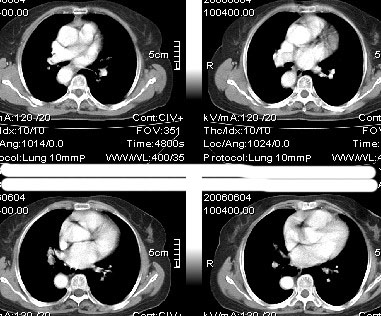

先天发育异常:降主动脉位右侧,主动脉弓形态欠规整。余未见异常影像。

主a弓及降主a都位于右侧,近膈肌时位于椎体前,,左室流出道及其他结构未见明显异常

右位主动脉弓伴迷走左锁骨下动脉。

楼主发布的是右主动脉弓的由中动脉弓并迷走左锁骨下动脉,并不是5楼战友说的全反位。

先天发育异常:右弓右降。